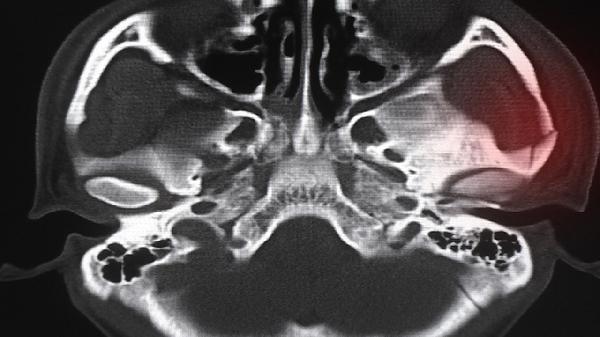

部分患儿可见肘关节轻度肿胀,桡骨头处可能有轻微隆起,患肢常保持内旋姿势。但典型畸形在外观上可能不明显,需通过X线检查确认桡骨头与肱骨小头的相对位置关系。